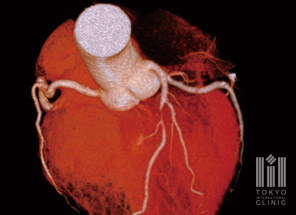

冠動脈CT検査

カテーテルを使用せずに冠動脈の画像を撮影します。検査時間も短く、心臓カテーテル検査に比べて負担が少なく検査できます。